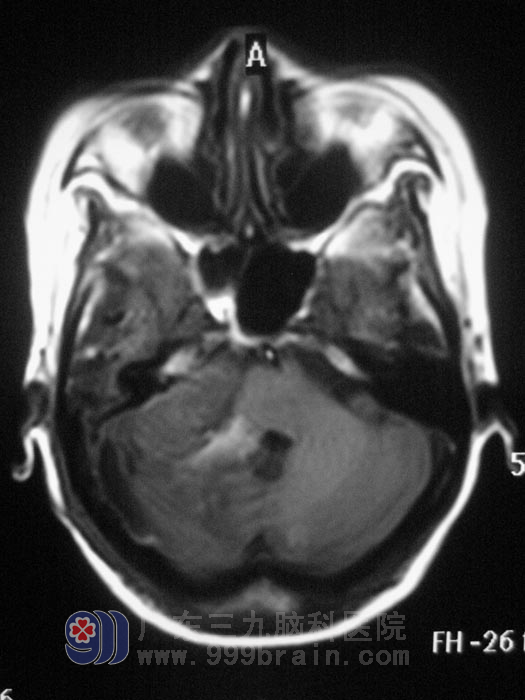

入住广东三九脑科医院综合神经外科时查体,右眼睁眼较左眼乏力,右侧额脸部痛温觉较左侧明显减弱,粗测听力右耳较左耳明显下降,复查头部MRI及MRA、MRV显示右侧桥小脑角区占位,脑干受压,肿瘤血供丰富,瘤内可见粗大血管,且靠近脑干,手术风险极高。

制订了精细的手术方案后,6月1日,由鲁明主任主刀,在全麻下为梅女士实施“桥小脑角肿瘤切除手术”, 术中见脑组织肿胀明显,肿瘤靠脑干侧血供极丰富,在显微镜下行肿瘤全切除。术后经过积极治疗,梅女士的耳鸣症状消失,右侧耳朵听力也有了很大改善。